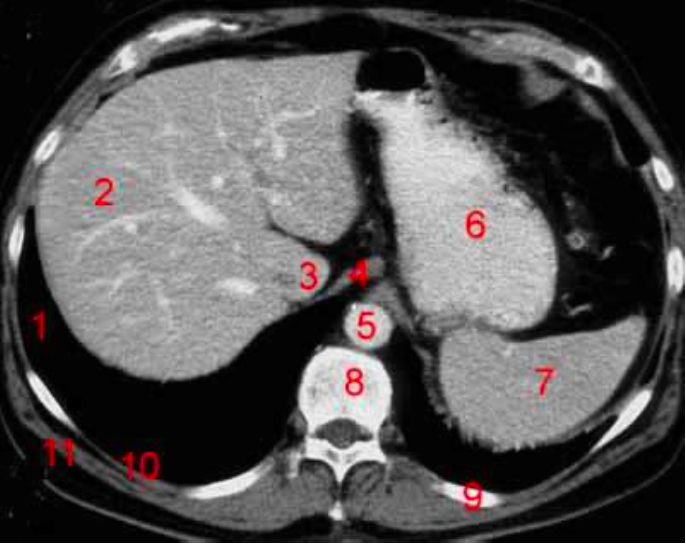

1

Number 3?

IVC

2

Number 1?

R Kidney

6

Number 8?

Body of thoracic vertebra

7

Number 9?

Lt rib

8

Number 7?

9

Number 4?

Rectus abdominus

10

Descending colon

11

Number 2?

Rt lobe of liver

12

Number 10?

Rt rib